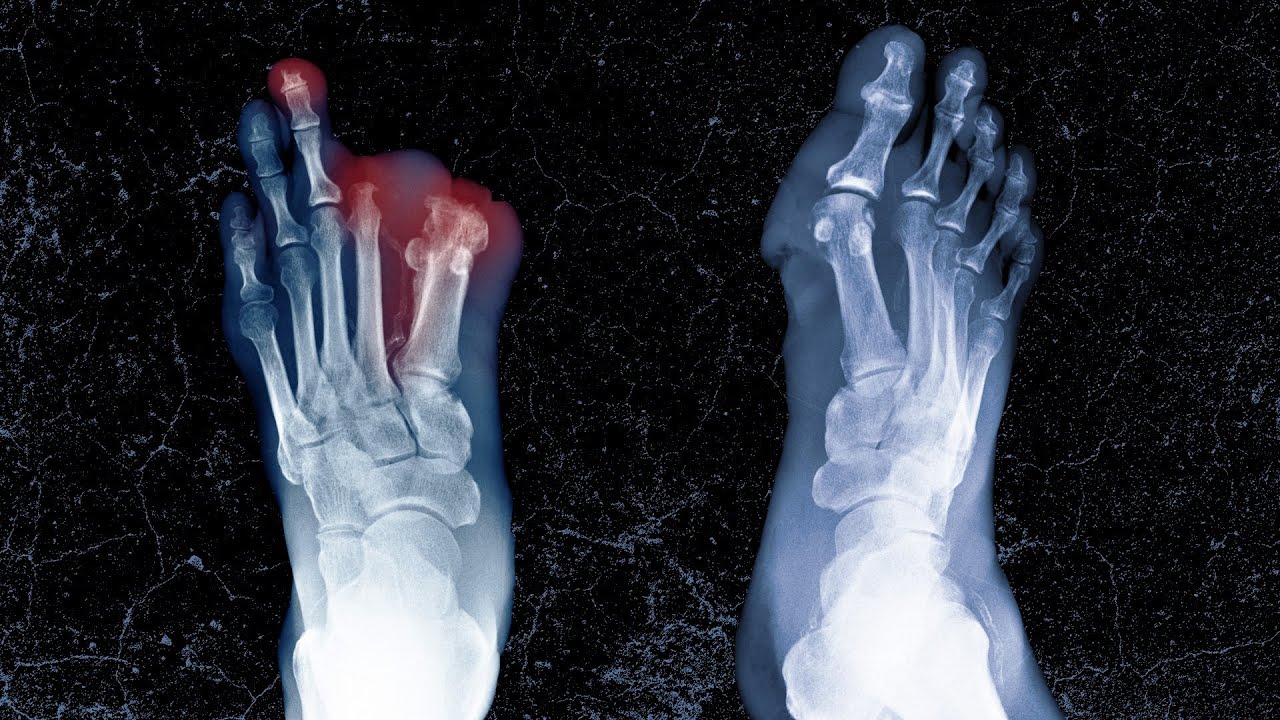

Η λοίμωξη οδήγησε σε Purpura fulminans, μια σπάνια θρομβωτική κατάσταση που προκαλεί τη διαστολή και την ανεξέλεγκτη πήξη των αιμοφόρων αγγείων, αποκόπτοντας το οξυγόνο από τους ιστούς και οδηγώντας σε γάγγραινα.

Αν και οι γιατροί κατάφεραν να σταθεροποιήσουν τη γενική του υγεία, η βλάβη στα άκρα του ήταν μη αναστρέψιμη.

Είχε δημιουργηθεί γάγγραινα, που οδήγησε στον ακρωτηριασμό και των δέκα δακτύλων του και των δύο ποδιών του κάτω από το γόνατο.